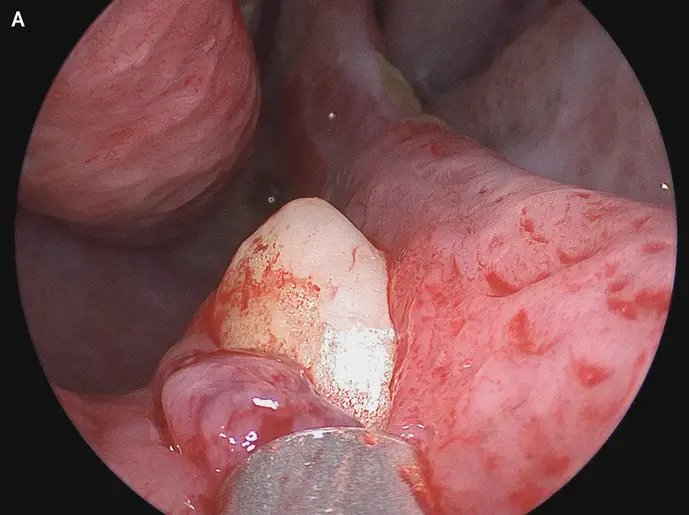

After performing a rhinoscopy, doctors were able to discover a white object lodged in his nostril.

It was then discovered that an ectopic tooth was, remarkably, growing in his nose.

Sagar Khanna and Michael Turner wrote in The New England Journal of Medicine: "Physical examination of the nose showed a septal deviation, calcified septal spurs, and a 2-cm perforation in the posterior septum.

"On rhinoscopy, a hard, nontender, white mass was observed in the floor of the right nostril (Panel A).